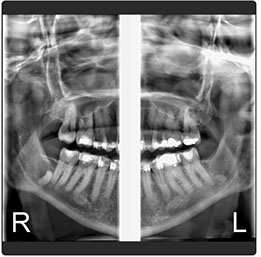

El Eagle 2D Pan/Tele ofrece todos los exámenes en el perfil panorámico (panorámica estándar, senos maxilares, baja dosis, bitewing, ATM, ortogonalidad perfeccionada, panorámica infantil y bitewing ortogonalidad perfeccionada) y todos los exámenes en el perfil cefalométrico (Posteroanterior, Antero-posterior, 45 Grados, Lateral, Carpal, PA de Walters, Axial Bazal, Hirtz).

La línea Eagle ofrece alta calidad de imagen, facilidad de operación, fácil posicionamiento del paciente y reúne lo mejor de la tecnología mundial en todas las funciones. El generador de rayos X de alta frecuencia reduce la exposición innecesaria del paciente. El sistema de microprocesado de alta velocidad y la mecánica precisa permiten la perfecta ejecución y repetición en imágenes 2D y 3D

Radiografía Panorámica Digital

Radiografía Panorámica